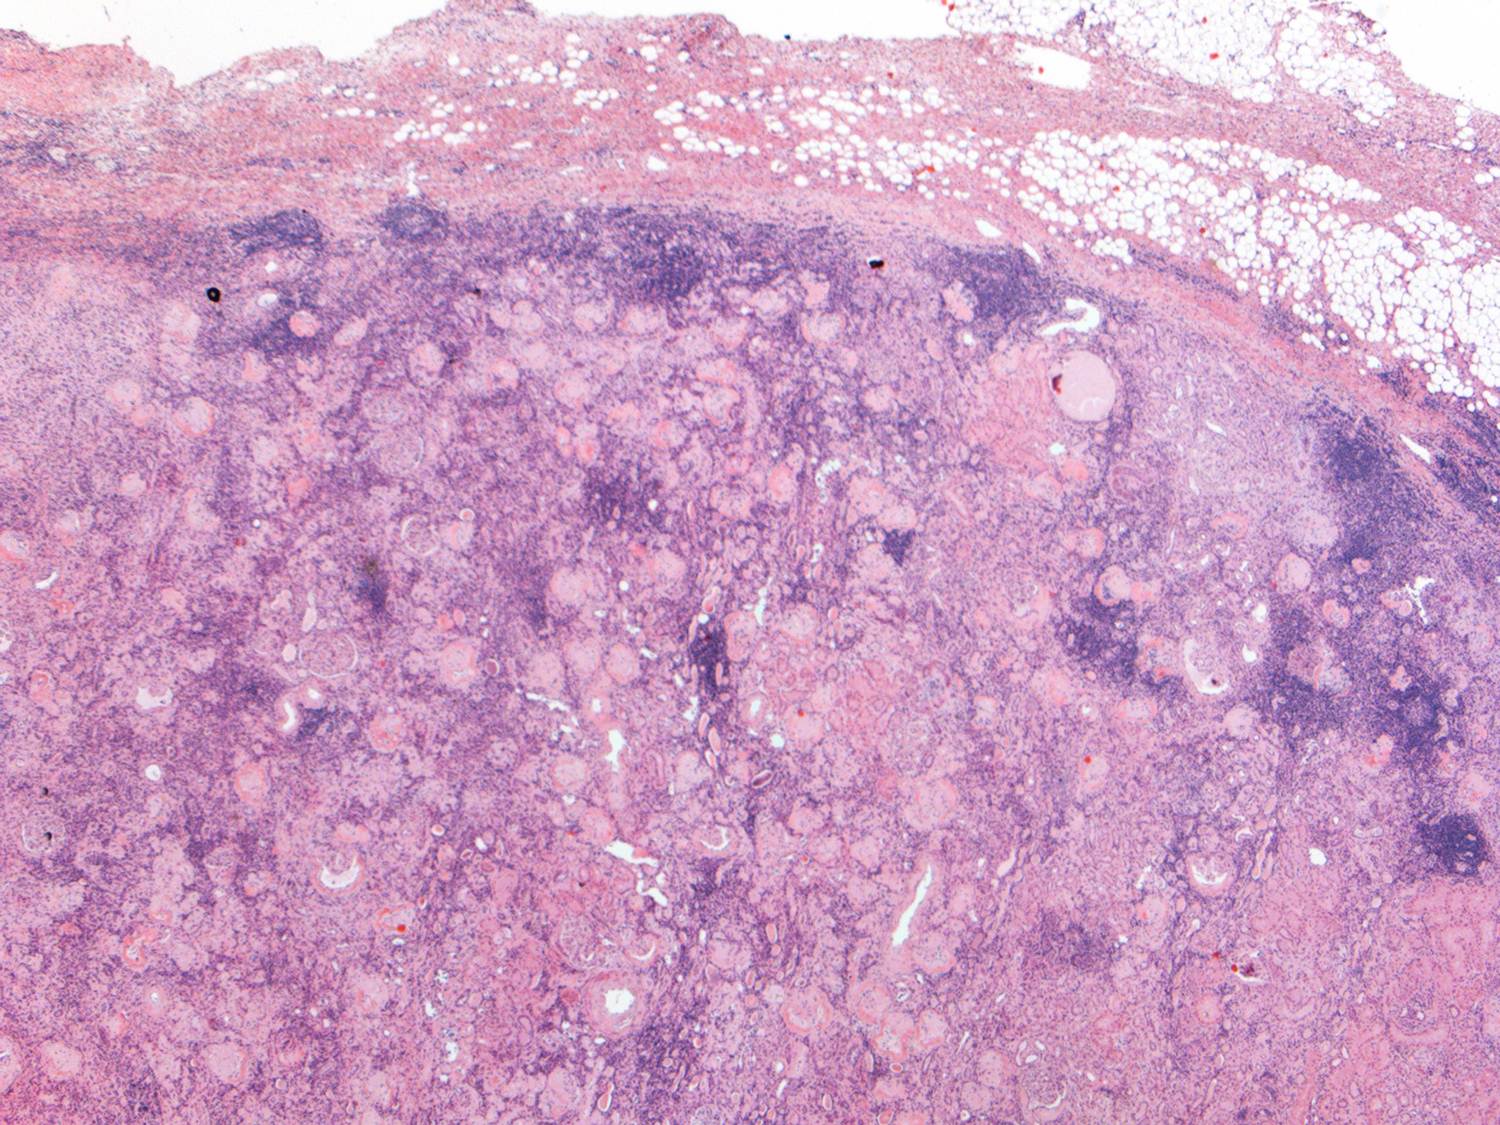

This is a low-power view of the renal cortex. There is diffuse global glomerulosclerosis involving approximately 80% of glomeruli. There is also significant tubular atrophy and interstitial fibrosis with associated areas of inflammation.

There was focal perirenal and intrarenal scarring with disruption of the renal capsule.

Higher power view of the preserved glomeruli revealed changes characteristic of diabetic nephropathy – nodular glomerulosclerosis.

Interestingly, he also had many tubules containing oxalate crystals, likely related to his previous gastric bypass surgery. There was associated acute tubular injury.